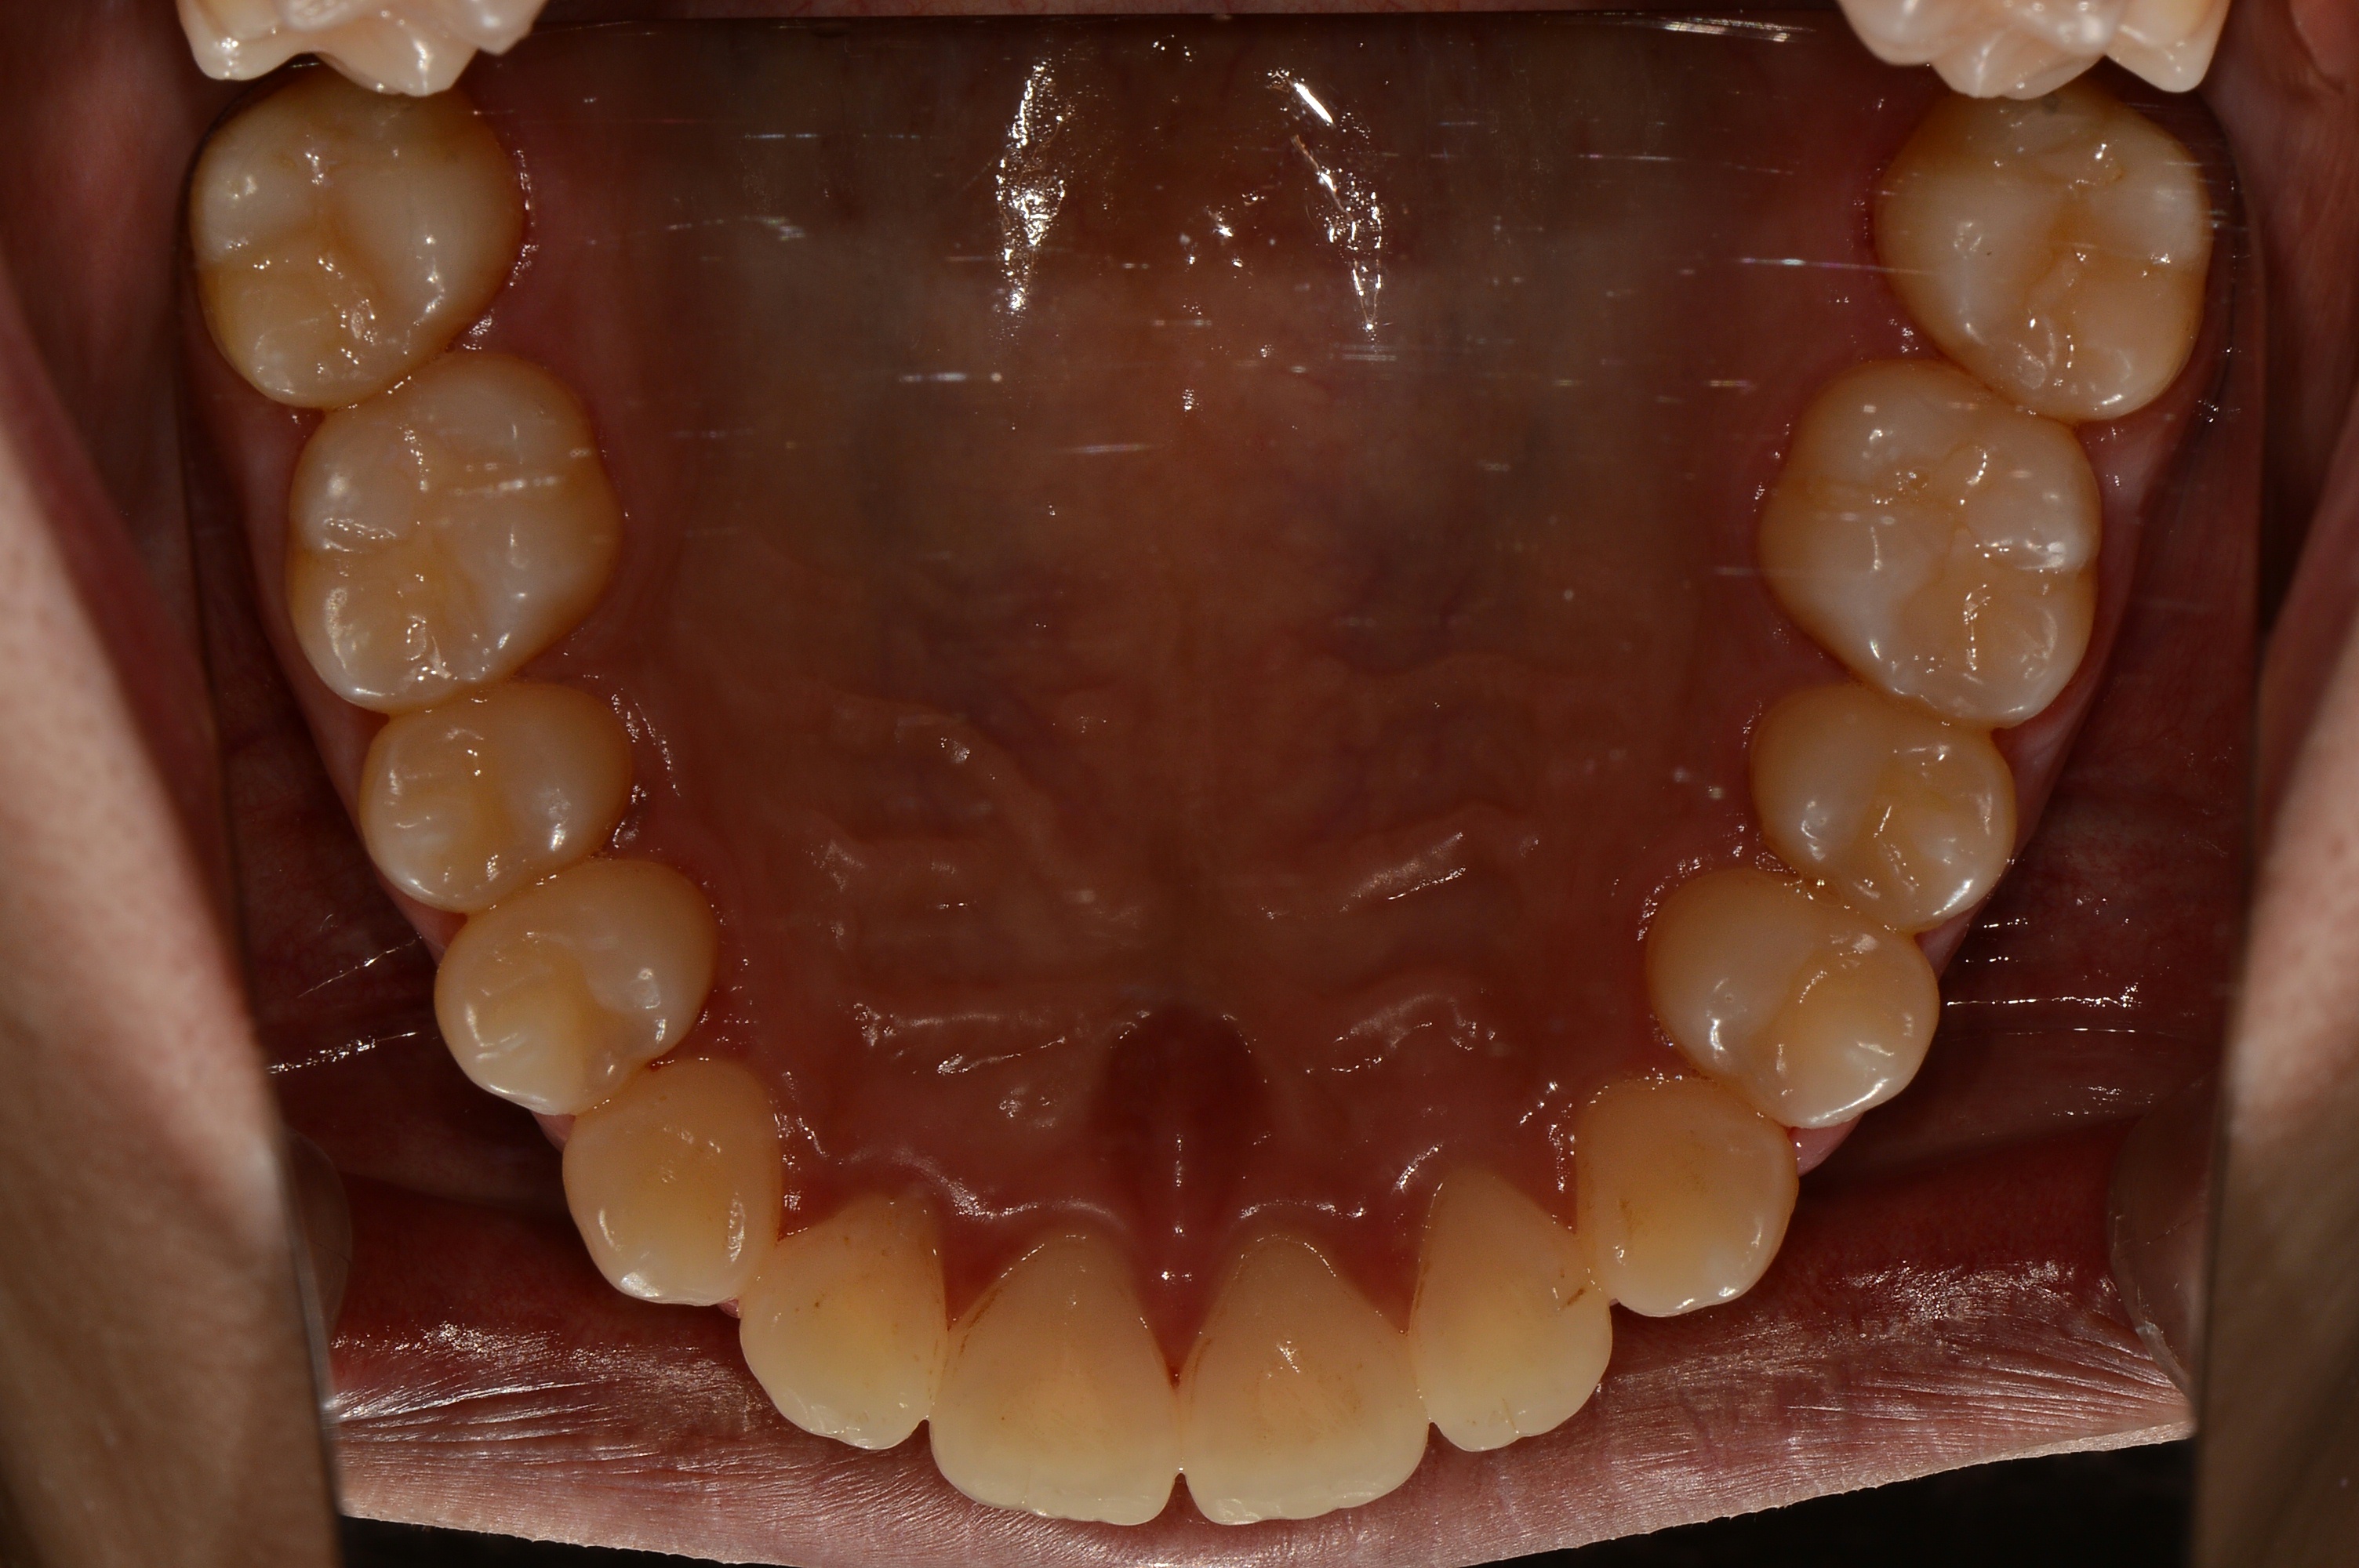

치료 후 사진입니다.